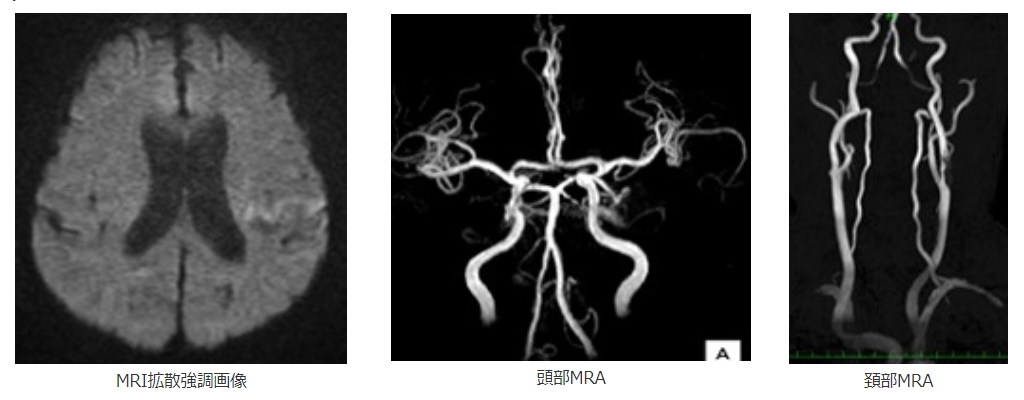

来院時診察を行い脳梗塞の重症度を判定します。そして頭部MRI画像などで脳血管の閉塞の確認、脳細胞が完全に死んでいる状態ではないことを確認します。

閉塞血管を再開通させれば症状が改善する見込みがある症例の場合はtPAの投与、血管内治療を検討します。点滴治療を行う場合は点滴を行いながら血管内治療を行います。